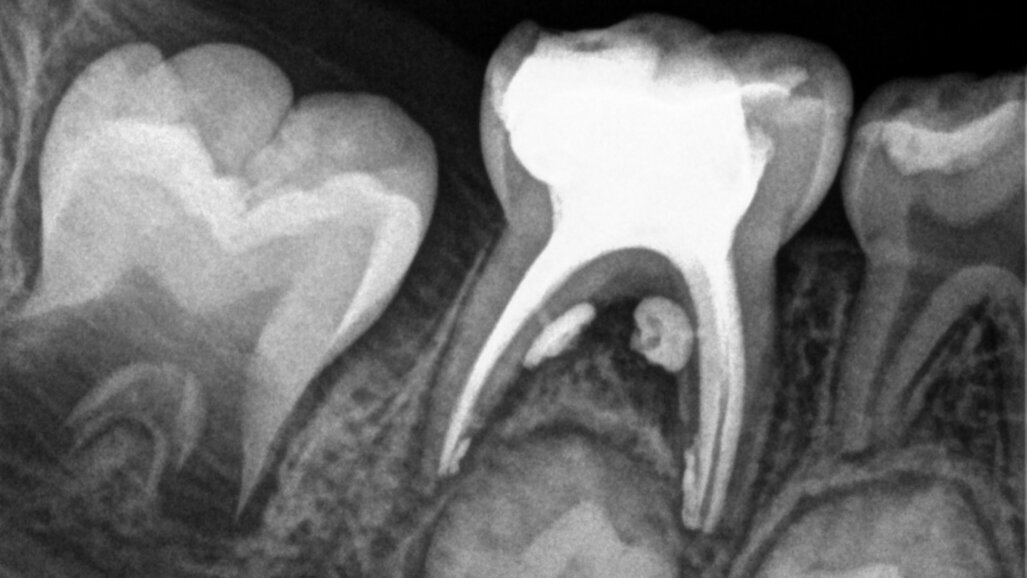

Cette patiente âgée de 4 ans et 7 mois présentait une douleur qui affectait la seconde molaire temporaire inférieure droite depuis plusieurs jours. L’examen clinique a révélé un gonflement du versant vestibulaire de la gencive et un œdème facial, ainsi qu’une carie occlusale profonde.Un diagnostic de nécrose pulpaire et d’abcès apical symptomatique ayant été posé, un traitement a été prescrit à la patiente, afin de maîtriser l’infection aiguë, et un nouveau rendez-vous a été fixé après l’antibiothérapie. Lors du deuxième rendez-vous, elle ne présentait plus aucune douleur et l’abcès buccal s’était partiellement résorbé. Il a été décidé de procéder à une pulpectomie et à la restauration de la dent. Dans ce cas, la dent présentait une extrusion excessive de matériau d’obturation. Après 15 mois, la réévaluation a confirmé l’absence de signes cliniques ou radiologiques pathologiques, et une apposition osseuse était visible dans la zone de la furcation.

Cas 1 (Figs 1-4)